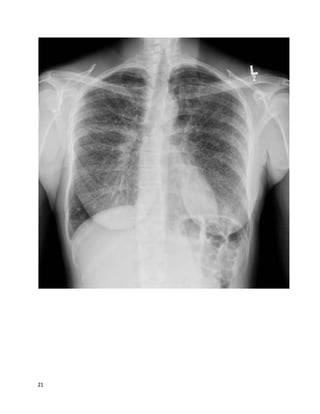

This 49 year old U.S. citizen originally from Trinidad is referred to you for

evaluation by her oncologist. She had the below chest X-ray after a mammogram

suggested abnormal lung parenchyma. Breast biopsy showed ductal carcinoma in

situ. She is to have lumpectomy soon. She has been mildly short of breath since her

20s, which has insidiously gotten worse, although she still works full-time and

takes care of 3 children. She also has a chronic dry cough worse on deep

20

inspiration. She has never sought evaluation for her symptoms and has never had

prior chest imaging. In your office, she walks 1000 feet in 6 minutes, with

desaturation from 100% on ambient air to 85% on ambulation with mild dyspnea.

A TB skin test is placed. An HIV test was negative last year.

PFTs:TLC 70% predicted (below lower limit of normal), FEV1/FVC ratio 0.65,

FEV1 2.1L (below lower limit of normal) DLCO 40% predicted, DLCO/VA 80%

predicted.

21

22

Without any other information, her most likely diagnosis is:

A. Idiopathic pulmonary fibrosis

B. Sarcoidosis

C. Tuberculosis

D. Lymphangitic spread of breast cancer

We feelthat B is the best answer.